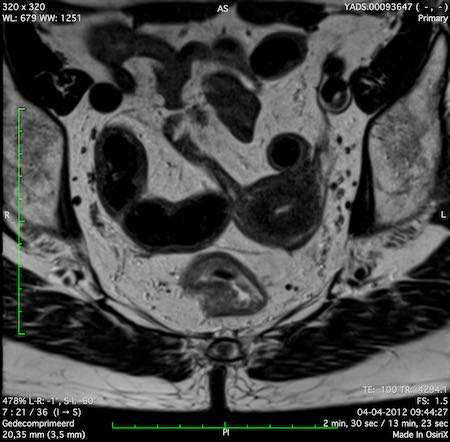

Hình ảnh

Các hình ảnh được cung cấp cho thấy ung thư biểu mô tế bào nhẫn với tình trạng dày lan tỏa thành trực tràng, hình ảnh bia bắn điển hình, và sự xâm lấn mỡ mạc treo trực tràng.